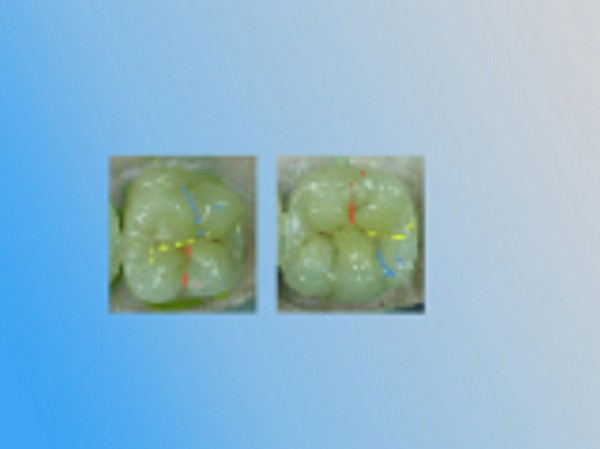

INTRODUCCIÓN El Bruxismo como entidad somática asociada al stress, responde a la mecánica de un Círculo Vicioso Patogénico, que Kawamura describiera hace ya muchos años. FACTOR DESENCADENANTE , que proveen las Interferencias a nivel dentario. En las entregas anteriores se desarrollaron las bases conceptuales de una OCLUSIÓN ORGÁNICA y los efectos de una mayor o menor Desoclusión según la variabilidad de los diferentes Factores Determinantes de la Oclusión. En síntesis; A-La obtención de una Oclusión en Relación Céntrica, nos permite devolver al sistema una elongación muscular fisiológica, sin acortamientos ni estiramientos musculares, sin las consecuentes estimulaciones de los husos neuro musculares, y; una situación estable de la A.T.M. con espacios articulares uniformes. B-El logro de una Guía Anterior que permita desocluir los sectores posteriores durante los movimientos excursivos, nos provée de una segunda y preponderante senda a transitar, que NO estimula por sus contactos excursivos la cincha Pterigo Maseterina, causante de las enormes destrucciones parafuncionales que es frecuente ver en bocas bruxómanas, y la axialización de las fuerzas sobre las piezas posteriores durante el cierre. C-Otorgando como consecuencia, Estabilidad a la tabla premolar-molar, simultaneidad en la recepción de fuerzas durante el cierre(A.T.M. y superficies oclusales). Obtendremos así una Oclusión estable y fisiológica, que no genere el FACTOR DESENCADENANTE del Bruxismo, siempre presente a nivel dentario. INTRODUCTION Bruxism as a somatic entity associated with stress responds to the mechanics of a Pathogenic Vicious Circle, described by Kawamura many years ago. Summarsing: A-Obtaining an oclusion in a Central Relation, allows us to return to the sistem a physiological muscular elongation, without muscular shotthenings or lenghthenings, without the following stimulations of the neuro-muscular huses and a stable situation of the Temporo Mandibular Joint with uniform articular spaces. B-The accomplishment of an Anterior Wide wich may allow disclusive the posterior sectors during the excursives movements, and the axial forces during the mandibular closure. C-Providing as a consecuence, axiality and stability to the posterior sections, responsible of the mandibular closure, through Sttopers, Equalitzers, A, B and C, to obtain a Oclusión Mutuamente Compartida: forces reception during mandibular closure (T.M.J. and Oclusal Surfaces) By this procedure, we should obtain a stable and physiological oclusion, that will not generate the chain link of factors that lead to Bruxism, always present at the dental level. MATERIALES Y MÉTODOS: La funciones articular y muscular, se analizaron mediante Bio Pack, en el pre, en el intra y en el post operatorio. Durante el diagnóstico, tratamiento y remontas, se utilizaron articuladores semi ajustables Wip Mix, totalmente ajustables Artex y arcos faciales correspondientes. El encerado de dianóstico se realizó, mediante la técnica de encerado progresivo de Peter K. Thomas. Los refuerzos a Perno Colado se llevaron a cabo con oro BIODENT YELLOW de ARGEDEN. Los tres juegos de provisionales utilizados, se hicieron con metacrilato termo curado. Las Restauraciones Periféricas Totales, fueron realizadas mediante porcelana CREATION de WILLY GUÉLLER, sobre oro BIODEN YELLOW de ARGEDEN. Los chequeos de los Contactos Interoclusales, se midieron con papeles de articular de 40 y 12 micrones, y mediante el analizador computarizado T-Scan. DESARROLLO Paciente varón de raza blanca, 42 años, complexión robusta y marcada hipertrofia maseterina. Fig.1 Fig.2 Fig.5 Se realiza un análisis pre-operatorio articular y muscular mediante Bio Pack, y oclusal mediante T-Scan, cuyos resultados muestran una evidente hiperactividad muscular en Temporal Anterior y Masetero Derechos, y contactos totalmente anómalos tanto en Oclusión Habitual como en Excéntricas. Fig. 6-7-8-9-10-11 Sensor de ruidos articulares Luego del primer intento de relajación mediante Laminillas de Long (Ref.6),Fig.12, registros y montaje, se observa la aparente presencia de una relación Borde a Borde, que luego se comprobaría que se trataba de una propulsión exagerada de su mandíbula en la búsqueda de contactos efectivos. Fig. 13-14 (Obsérvese el fenómeno de Patterson dado por la exclusiva guía de movimiento de la A.T.M. y la carencia de la Guía Anterior) Se procede a construir un JIG de LUCIA para lograr una desprogramación muscular adecuada, y se le indica permanecer con el colocado durante toda la noche anterior a la consulta, sin contactos dentarios posteriores. Aún en la duda, de que la obtenida sea una posición articular fisiológica, se procede a construir una Placa de Relajación sobre el último montaje obtenido, la que se ajusta cada dos días, y al cabo de tres semanas se procede a un tercer montaje obtenido de la nueva situación posicional. Fig.17-18 Se verifica entonces que estamos en realidad, ante una presunta CLASE II, después de tres métodos diferentes de relajación y transcurridos más de un més de múltiples sesiones para lograr una posición diagnóstica confiable a partir de donde comenzar a trabajar.(O.R.C.) Se adicionan entonces topes (montículos) en las caras oclusales de los primeros molares de la Placa de relajación, transformándola en una Férula Pivotante, de levísima altura, impidiendo el contacto de las demás piezas dentarias a fin de convertir la palanca en una de clase II (fisiológicamente el sistema se mueve según una palanca de clase III), y obtener de esa forma una descompresión de los espacios articulares, ya que si bien la A.T.M. era asintomática, estaba muy claro que la Dimensión Vertical Posterior se presentaba disminuida debido al exagerado desgaste de todos los sectores posteriores, cuya típica forma de «desgaste en olla», se verificaba en el análisis estático de los modelos.( Ref.7) En esa situación se remonta el modelo inferior puesto que el superior no modifica su posición espacial, y se realiza un Encerado de Progresivo Diagnóstico según PKT, previo análisis de los modelos mediante los analizadores de W.McHorris (Ref.8) Fig.18-19-20-21-22-23-24-25-26-27-28-29-30 Fig.18 Fig.22 Fig.23 (Obsérvese, que la Disclusión Propulsiva comienza en los rebordes mesiales del canino, sigue en los rebordes distales del lateral, y finaliza con los rebordes mesiales de los centrales.) Se realizan las endodoncias de toda la boca y se tallan los endodontos para la construcción de Pernos Muñones Colados de oro, los que se realizarán mediante técnica indirecta sobre los modelos :montados según los logros de todos los procedimientos de relajación. Se torna imprescindible la extracción de tres piezas dentarias, para la confección de la Guía Anterior, cuyo alineamiento hubiera sido imposible mediante técnicas reconstructivas ya que la posibilidad ortodóntica no era viable dadas las condiciones de desgaste. Fig.31-32-33-34-35-36-37 (Obsérvese, que desde la configuración de los Pernos Muñones Colados, se determina ya la Alineación Tridimensional que otorgaremos a la Rehabilitación Oral Integral del caso. Se monta entonces el primer juego de Provisionales de acrílico de termo curado, obtenido de la réplica del Encerado de Diagnóstico. Fig.38-39-40-41 (Obsérvese la presencia del ajuste periférico y las disclusiones, tan importantes en las provisorias como en las definitivas ya que del resultado de la etapa de provisionales, dependerá el éxito final.) Se ajustan las Unidades de Oclusión mediante Ajuste Oclusal (según técnica propuesta por la Cátedra de Operatoria Dental II y Prótesis de la Fac. de Odontología, Univ. Bs. As., Prof.Anibal Alonso.) Se deja actuando la nueva situación durante seis meses. Han transcurrido seis meses durante los cuales se instaló un nuevo juego de provisorios con las mismas características del anterior, y clinicamente no se observa hiperactividad muscular, perforaciones de los provisorios, molestias para desmenuzar los alimentos ni síntomas alguno en la A.T.M. NOS ENCONTRAMOS, CON UN SISTEMA EN PAZ A TODOS SUS NIVELES. Se procede entonces a la toma de impresiones definitivas, mediante la técnica de Impresión a Presión Masticatoria, para la confección de las restauraciones permanentes, y los metales se chequean mediante llaves de Duralay, para observar la situación análoga entre laboratorio y clínica.(Corroboración de la Oclusión en Relación Céntrica)Fig.42-43-44 Se prueban los metales y verifica su ajuste periférico. (Obsérvese que también en los metales sub porcelana se siguen las formas de las Preparaciones Funcionales, permitiendo de esta manera un perfecto bizcochado de la porcelana supra metal.) Realizada la Guía Anterior, Determinante Oclusal Primario y Anterior en el laboratorio, se prueban en boca sus características estáticas: Altura Funcional, Ángulo de la Disclusión y Punto de Acoplamiento, como así las dinámicas: Laterotrusión Derecha e Izquierda y Propulsión. En este estado las cosas, tenemos al sistema circunscripto tanto estática, como dinámicamente, por el gobierno de dos comandos, ya en Oclusión en Relación Céntrica, como en las Transtrusiones: Sabemos que todo lo que construyamos (tabla premolar-molar), entre estos dos comandos rectores del movimiento, partirán del mismo punto y volverán a el, transitando el recorrido impuesto por los mismos. Se construyen entonces en el laboratorio, las unidades de oclusión de premolares y molares, siendo las correspondientes a los cuatro últimos molares, con oclusal en oro, como un elemento de detención del cierre más poderoso que la porcelana.47-48-49-50-51 Se prueban en boca la Curva de Wilson, la Curva de Spee, la Alineación Tridimensional, los Espacios Uniformes Disclusivos, la Dirección de los Surcos de T, nT, y P, y los Puntos Interoclusales de Contacto. En laboratorio se retocan entonces los Puntos Interoclusales de contacto, acercando los mismo a la mejor posición ideal lograble, y luego de una nueva prueba en boca, se glacéan las piezas y se instalan en forma provisional durante 24 hs. Verificada la eficacia de las formas (FORMA=FUNCIÓN), se procede a constatar la eficiencia de la dinámica trayectorial y se cementan con cemento de fosfato mediante la técnica de cementado alterno. Fig.54-55-56-57-58-59-60-61-62-63-64-65-66-67-68-69. Fig.54 Fig.55 Curva de Wilson y Alineación Tridimensional en molares y premolares sup. Der. Fig.56 Fig.57 idem inferiores derechos Fig.58 Fig.59 Idem superiores izquierdos CONTACTOS INTEROCLUSALES SUPERIORES CONTACTOS INTEROCLUSALES INFERIORES Transcurrido un mes de instalada la Rehabilitación, se lleva a cabo un nuevo estudio, post operatorio con Bio Pack y Tscan. CONCLUSIONES : I-El paciente realiza una apertura bucal de 45mm sin forzamientos siguiendo una misma línea de apertura sin desvíos. II-Las disclusiones en laterotrusión se llevan a cabo mediante un recorrido lineal sobre los rebordes medios de ambos caninos superiores, creando un fenómeno de Luce con espacios uniformes en ambos lados. III-La disclusión en propulsión se manifiesta comenzando en los rebordes mesiales de ambos caninos, siguiendo por los rebordes distales de laterales y terminando en los rebordes mesiales de ambos centrales, dando lugar a un fenómeno de Christensen con espacios uniformes de ambos lados. IV-Los contactos interoclusales son suficientes, simultáneos y tripódicos logrando la estabilidad en ambos planos del espacio tanto de las piezas individuales como en conjunto, sin contactos deflectivos. V-Realizado un nuevo montaje de la boca terminada, corroboramos como estable la Oclusión en Relación Céntrica. VI-No existen movilidades dentarias y los tejidos periodontales y gingivales se encuentran estabilizados. VII-No existen ruidos articulares. VIII-El resultado post operatorio Bio Pack de la dinámica mandibular, muestra una sustancial mejora de los movimientos en los tres planos del espacio. IX-Electromiográficamente, se observan contracciones musculares dentro de los rangos de normalidad, persistiendo un rango ligeramente elevado en temporal anterior y masetero del lado derecho, presumiblemente debido a la hipertrofia que dicho paciente traía, y mostraba en el estudio pre-operatorio. COMPARACIONES PRE, INTRA Y POST OPERATORIAS Sonografía de la ATM: Tanto en el examen pre como post operatorio no se observaron ruidos de ningún tipo, coincidiendo con la exploración clínica pre auricular e intra auricular. Electromiografía: La electromiografía en reposo, muestra bien a las claras la presencia de músculos hipertónicos durante el estudio pre operatorio, fundamentalmente del grupo Temporal Anterior y Digástricos, estando el Masetero izquierdo ligeramente por encima de su rango normal como así también ambos Esternocleidomastoideos. Durante el estudio post operatorio, se verifica el estado tónico de todos los grupos musculares, persistiendo una ligera hipertonicidad de rango levemente por encima de lo fisiológico, en el Temporal Anterior Derecho y Digástrico Derecho. PRE OPERATORIO POST OPERATORIO Temporal Ant. Der. 4.4 2.8 Temporal Ant. Izq. 6.2 1.1 Masetero Der. 1.2 0.5 Masetero Izq. 1.5 0.8 Est.Cleid.Mast. Der. 1.6 0.3 Est.Cleid.Mast. Izq. 2.1 0.2 Digástrico Der. 1.7 2.9 Digástrico Izq. 1.6 0.7 (La unidad de medida utilizada es el microvoltio ) Dinámica mandibular: Durante el Pre Operatorio, en el Plano Sagital, tanto la Apertura como el Cierre lento, se manifiesta mediante una acentuada tendencia a propulsar la mandibula. Durante el Post Operatorio, la tendencia hacia la derecha de estos dos últimos planos se mantiene, mientras que en Plano Sagital, la propulsión inicial no se produce, asemejándose el movimiento a la primera fase del Bicuspóide de Posselt. El Análisis de la Dinámica realizado durante la Masticación (chicle), nos muestra en el Plano Sagital, la propulsión mencionada durante la apertura y cierre lentos durante el estudio Pre Operatorio, se aproxima a la normalidad durante el Intra Operatorio (2º juego de provisionales), y se vuelve a manifestar propulsivo, en el Post Operatorio. En cuanto al Plano Frontal, durante el Pre Op. , ofrece un Ciclo Masticatorio(recordar la forma de «gota de agua») para el lado izq., con componentes derechos e izquierdos alternos, que se aproximan paulatinamente al Ciclo Masticatorio Normal, durante el Intra y Post Operatorio. El Plano horizontal, confirma las afirmaciones anteriores durante los tres períodos de estudio. ANÁLISIS MEDIANTE TSCAN 1-Bio Pack Bio Research Associates,Inc Distrib.UEDA S.A. 2-Wip Mix-Artex 3-Au:89% / Pt:6% /Elementos complementarios:5% 4-Idem ref.3 5-Tscan TekSkan,Inc Distrib.UEDA S.A. 6-Mc Horris.Cátedra de Operatoria Dental II y Prótesis. 7-Alonso.Cátedra de Operatoria Dental II y prótesis. 8-Mc.Horris. Analizadores de Guía Anterior. BIBLIOGRAFÍA: 1-Esquemas de las dos primeras entregas, tomadas del libro:»Oclusión Orgánica…un camino hacia la Rehabilitación Oral» 2-Oclusión y Diagnóstico en Rehabilitación Oral. 3-Anatomia Odontológica. 4-A contribution to the study of the movementes of the mandible. 5-Celenza F.W, Nadeskin J.F.,Oclusión.Situación actual. 6-D´Amico 7-Dawson P.E. 8-Huffman -Regenos. 9-Hobo S.-Takayama H.A. 10-Lucia V.O 11-Mc Horris. 12-Mc Horris. 13-Posselt U. 14-Stuart C. 15-Vartan Veshnilian AGRADECIMIENTOS: La Rehabilitación Oral, especialidad donde se hace imprescindible el manejo y concurrencia de todas las especialidades dentales en su desarrollo más depurado, no tendría razón de ser, sin la más estrecha colaboración de una técnica para- médica con detalles de excelencia. Sr. Pedro Colomina: muchas gracias. Pedro Colomina. – Titulado especialista en prótesis dental en la escuela Ramon y Cajal de Barcelona 1988

Oclusión en Relación Céntrica

(Derecha)

Fig.24

Disclusión Canina

(Derecha)

Fig.25

Oclusión en Relación Céntrica

(Izquierda)

Fig.26

Disclusión Canina

(Izquierda)

Fig.27

Al cabo de los mismos se realiza una nueva comprobación del estado articular y muscular mediante Bio Pack y un chequeo oclusal mediante T-Scan, donde se observan una evidente mejoría de la musculatura comprometida, de la dinámica mandibular, de la apertura bucal, de los contactos simultáneos de la Oclusión en Relación Céntrica como así de las Excéntricas, y un manifiesto control masticatorio por parte del paciente.

Durante esta última, se obtiene un comienzo en los rebordes mesiales caninos, luego los laterales y por último los centrales, tal como se concibió en el encerado.

Se confirma nuevamente la centricidad mandibular a través del contacto canino simultaneo, y se toma con la G.A. instalada (comando anterior de la desoclusión), un nuevo registro intermaxilar. Fig.45-46

Guía Canina-Lado de Trabajo derecho

Fig.63

Guía Canina-Lado de Trabajo izquierdo

Fig.64

Guía Anterior sobre Rebordes Palatinos Superiores